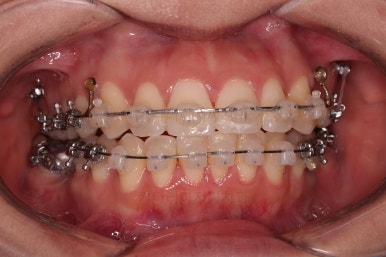

전후 비교 해볼게요.

입안의 모습은 더할나위 없이 잘 개선되었고요.

상하좌우 이 뽑은 위치와 크기가 달라 이정도 중앙선은 매우 잘 맞는 상황인거고요.

얼굴모습도 옆라인이 매우 좋아졌죠.

입이 들어가고 턱선이 살아나게끔 해드렸어요.

임플란트도 안해도 되면서 사랑니까지 잘 사용하고 2년 반 밖에 치료기간도 안걸린 매우 좋은 치료였다고 생각되어집니다.

이상 어금니가 결손되어 있고, 돌출입이었던 환자분을 미니스크류를 이용해 사랑니까지 당겨와서 임플란트 없이 치료를 한 부산사랑니교정 치료사례였습니다.